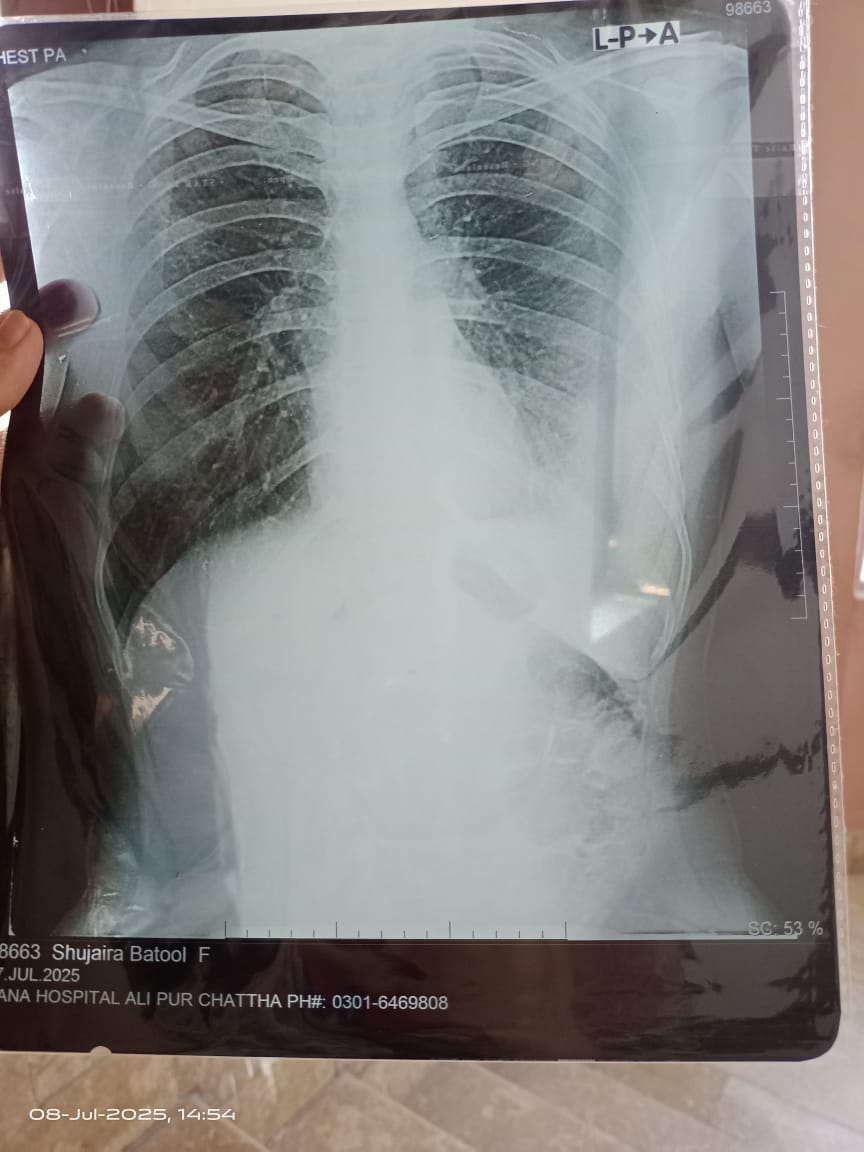

Left sided Pleural Effusion hai.

There is fluid around left lung which is called Pleural Effusion. Fluid should be tested to find the cause

fluid in left lung

needs to find the cause

left side effusion. take consultation from a pulmonologist urgently

left side pleural effusion need to aspiration for diagnostic, take appointment

left side effusion need in clinic appointment for further management